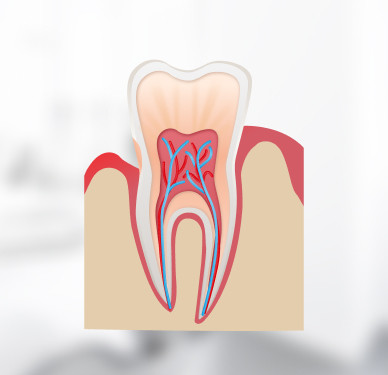

Наши пациенты не испытывают дискомфорт во время лечения. Мы используем метод Icon, при котором сверление зуба не требуется.

Метод основан на принципе инфильтрации. Вместо сверления врач использует специальный гель, содержащий соляную кислоту, который растворяет поражённые ткани. Затем стоматолог послойно наносит инфильтрат, чтобы «запечатать» кариозную полость. При этом здоровые ткани зуба остаются невредимыми!

Метод Icon подходит для лечения кариеса на ранней стадии. Это ещё раз доказывает необходимость своевременного посещения стоматолога. Чем раньше вы обратитесь за помощью, тем проще будет лечение.